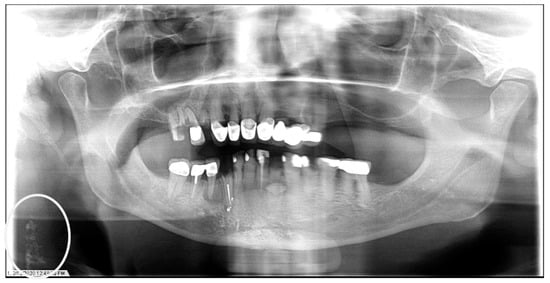

Figure 3.

The panoramic radiograph of an 80-year-old male patient with a medical history of hyperlipidemia and diabetes mellitus showing bilateral carotid artery calcifications (CACs) during a comprehensive dental examination. The CACs are encircled by a white line.